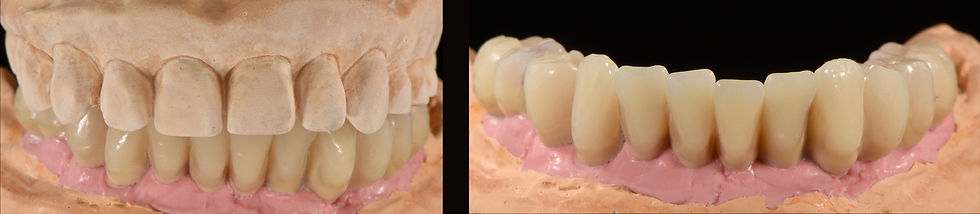

Relation between the two jaws on laboratory model

Provisional framework

Provisional prosthesis

Provisional prosthesis polished